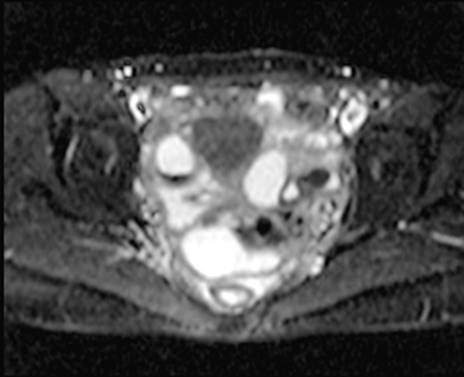

【症例】40歳代女性

【主訴】上下腹部痛

【現病歴】2日目から下腹部痛あり。夜間は痛みで眠れなかった。昨日より上腹部痛と下痢が出現。臥位で痛みは軽快したため、休んでいた。本日になって臥位でも立位でも痛みが強くなってきたため救急要請。

【既往歴】子宮内膜症

【身体所見】部:平坦・軟、左上下腹部に圧痛あり、反跳痛あり。

【データ】WBC 21800、CRP 26.78

MRI(4日後)